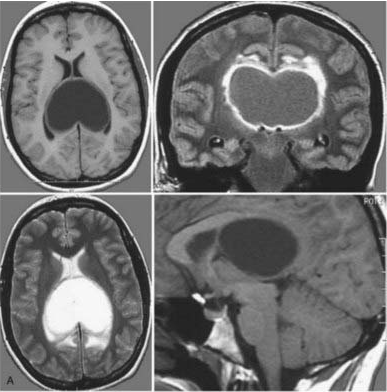

33岁孕妇Olive在孕期出现严重头痛、行走不稳及轻度记忆减退症状。检查发现双侧侧脑室存在巨大肿瘤,并合并脑积水症状。考虑到患者情况,立即进行囊液引流和肿瘤活检以降低颅内压。活检结果显示为毛细胞型星形细胞瘤,Olive症状迅速缓解,妊娠期间无需进一步治疗。

MRI影像学表现:轴位(左上、左下)、冠状位(右上)和矢状位(右下)序列显示一个大型囊性肿瘤占据双侧侧脑室后部。尽管肿瘤体积巨大,但Olive最终顺利分娩。后续由INC巴特朗菲教授实施手术,肿瘤被完全切除,同时保留双侧胼胝体结构。术后患者出现轻度记忆减退,持续数周后缓解;未出现任何神经或认知功能缺损。随访MRI显示肿瘤无复发征象。